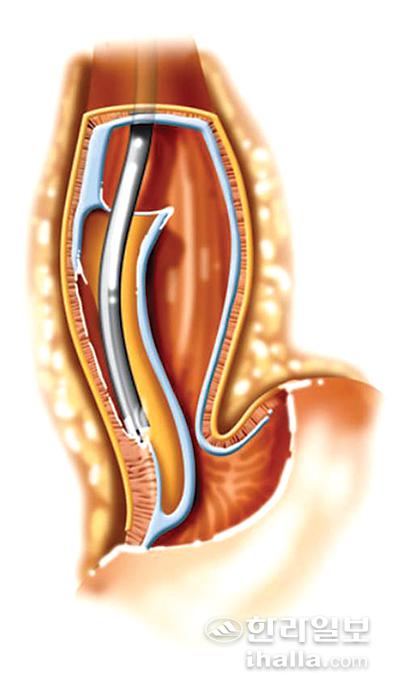

식도 안쪽에 작은 구멍을 내어 점막 하층으로 내시경을 진입한 후 식도의 근육을 절개한다.